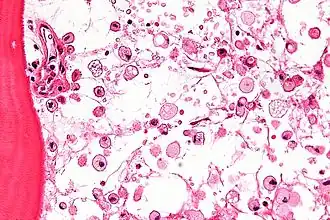

On dénombre une cinquantaine de maladies lysosomales, dont le point commun est une déficience génétique aboutissant au dysfonctionnement du lysosome. Les lysosomes sont des organites du cytoplasme qui contiennent des enzymes (spécifiquement, des hydrolases acides) qui sont chargées d'assimiler les déchets (appelés métabolites) produits par les cellules. Cette assimilation est le travail de protéines produites par le lysosome. Pour chacune des maladies lysosomales, un défaut d'un gène spécifique entraîne la non-production ou la production insuffisante de la protéine chargée de l'assimilation des métabolites.

Les métabolites s'accumulent alors, entraînant le dysfonctionnement des organes concernés. La plupart de ces maladies sont évolutives et polyhandicapantes. Elles entraînent des handicaps physiques, et neurologiques pour certaines d'entre elles. Il s'agit dans tous les cas de maladies rares.